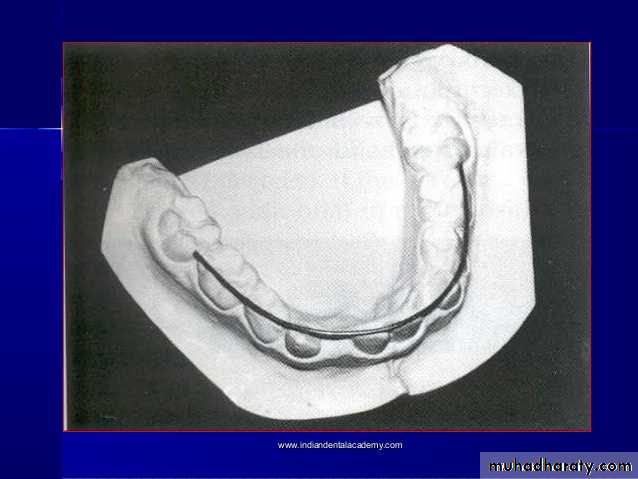

Cast analysis1.Arch Length &Arch Perimeter analysis

• dental space Analysis : Arch Required Arch Available

Arch space= Arch Required - Arch Available

Requirements to do cast analysis

• Well prepared study models• Vernier calipers

• Divider

• Ruler

• Brass wire